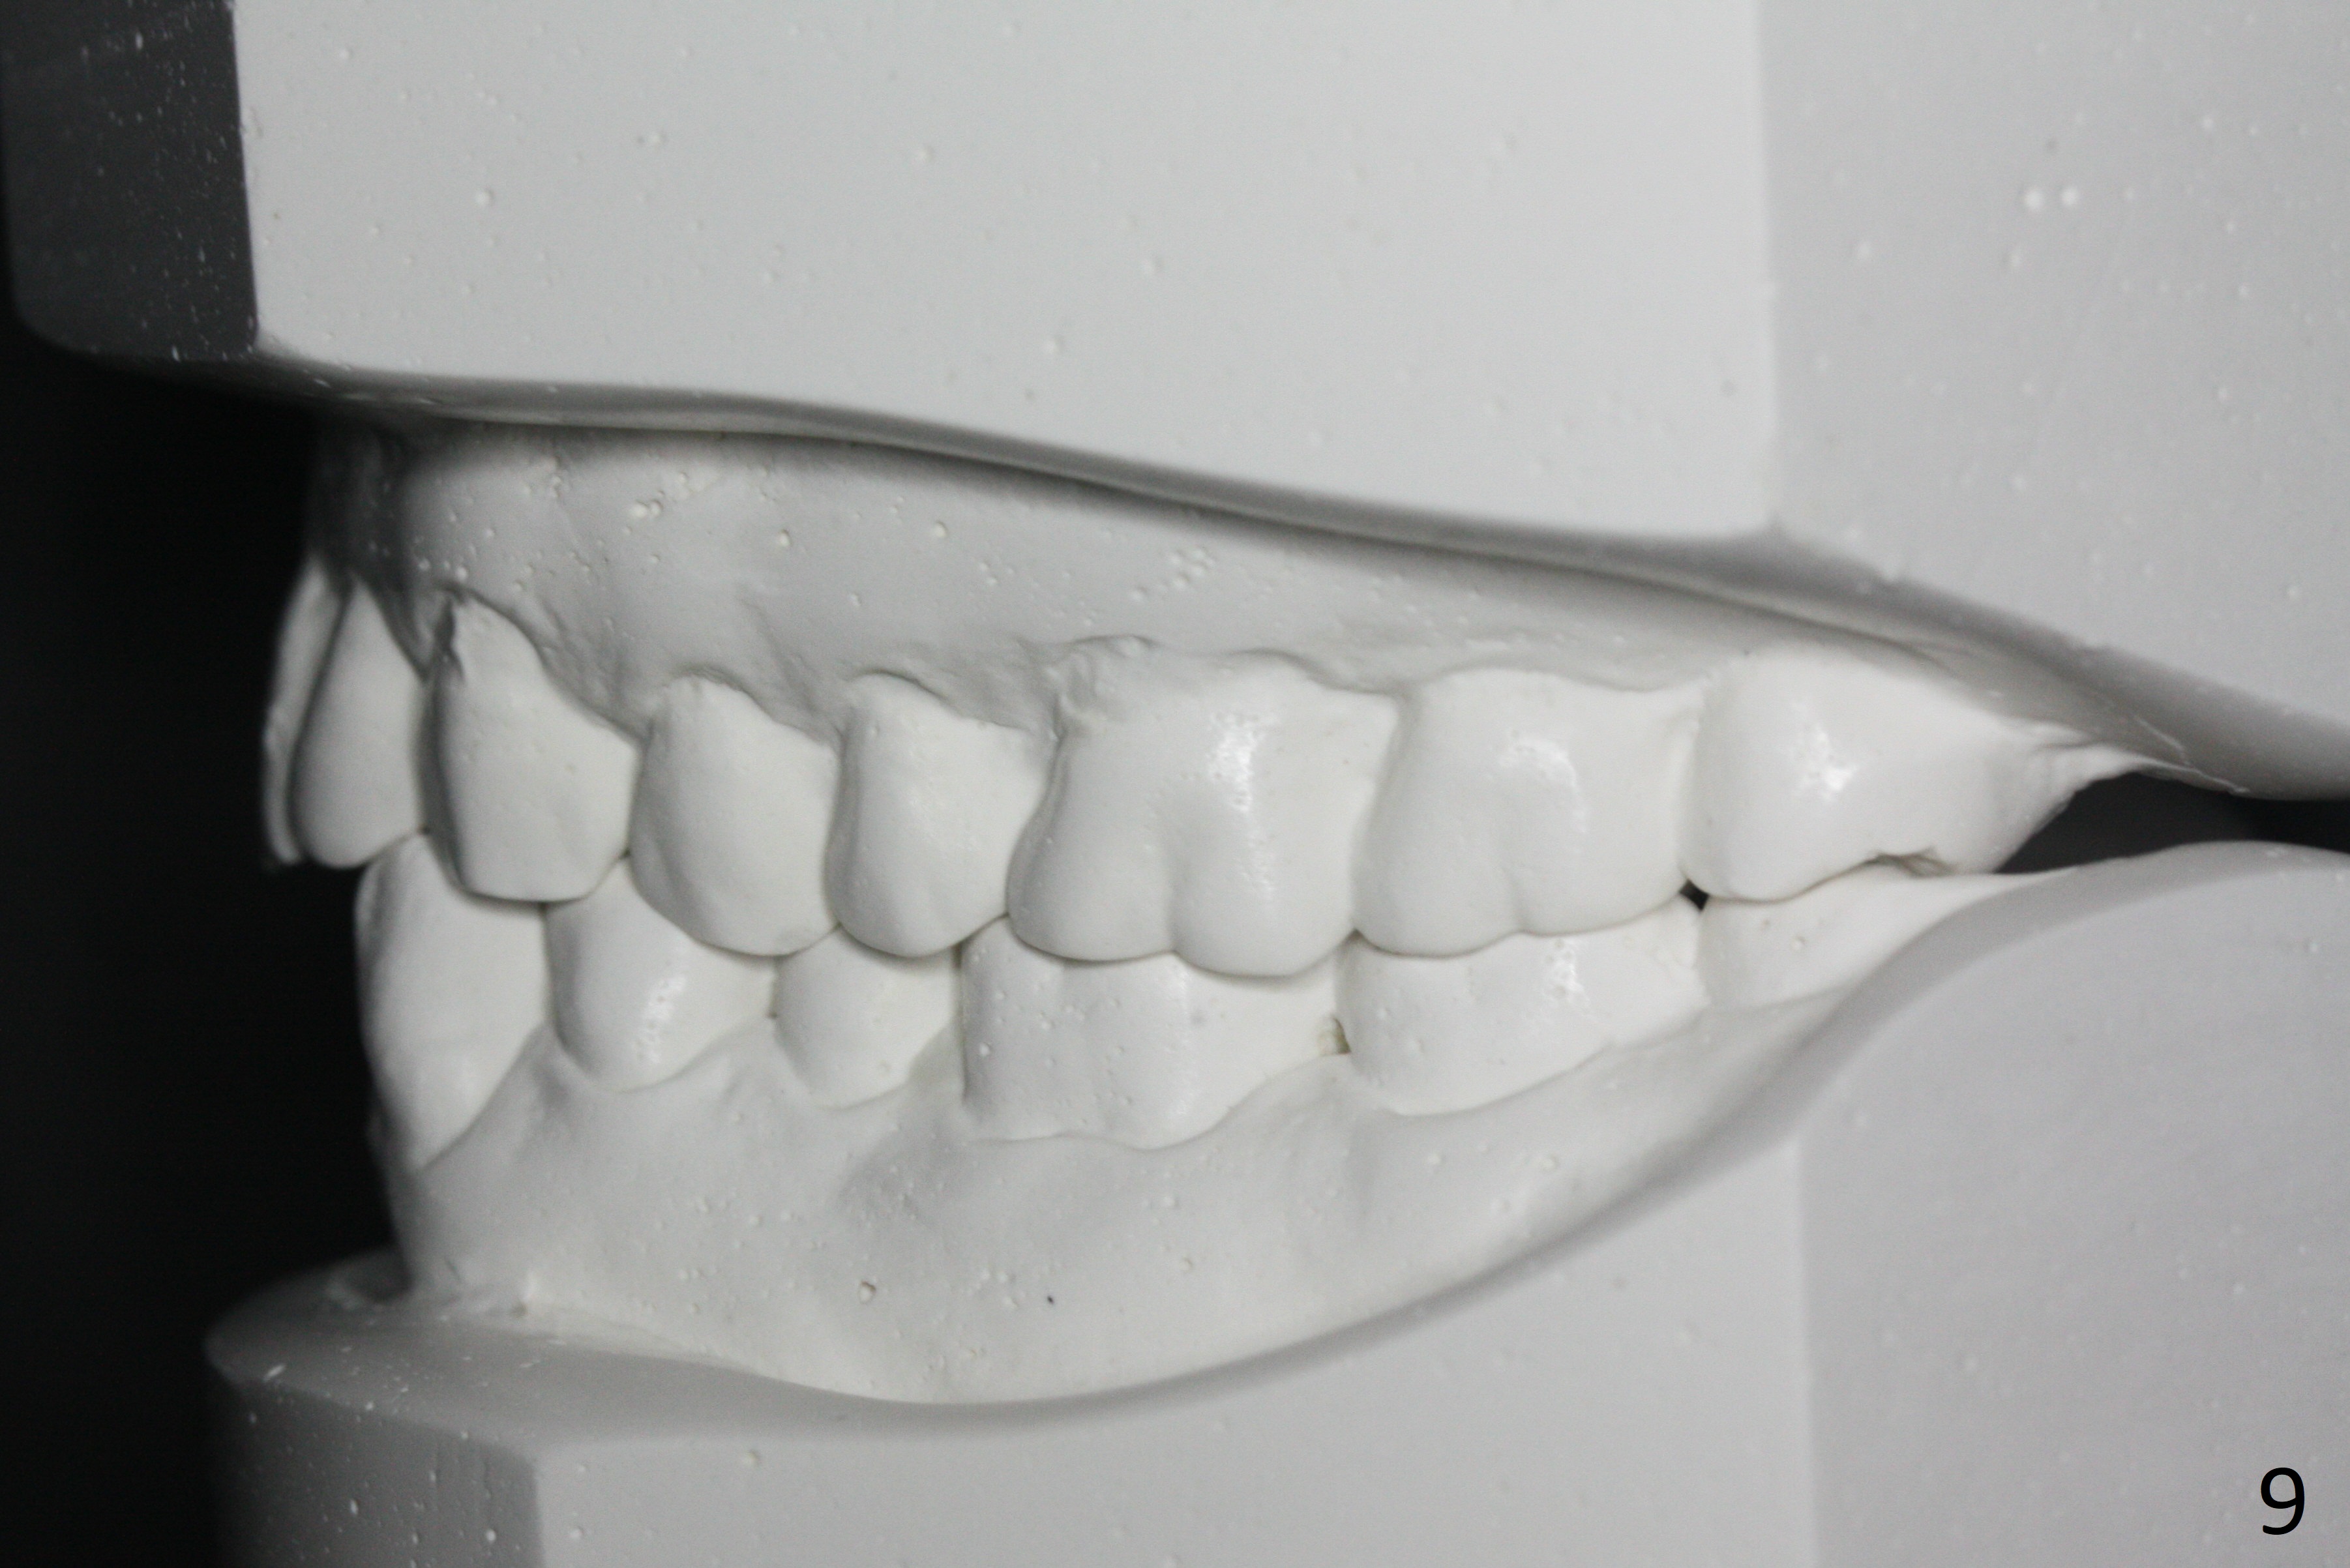

Enough Space For Crowding After Extraction? A 47-year-old man requests orthodontic treatment following SRP in other office (Fig.1-11). For severe crowding and midline shifting, extraction of four of the 1st bicuspids is imminent. Is it enough? To answer the question, model surgery is performed (Fig.12-16). 1st visit: periodontal maintenance, orthodontic consent (emphasizing oral hygiene) extract 4s and possibly L8s and separators. The beauty of this vist is that after local anesthesia and extraction including L8s, it is painless and easy to remove calculus from the proximal surfaces of the neighboring teeth. It is much easier to place separators after extraction. It is expected that there is no gingival erythema when the patient returns for bracketing. Take photos of UR3, similar to Fig.3. Molar banding is also anticipated to be easy with separator placement after extraction. Return to Ortho Cases Xin Wei, DDS, PhD, MS 1st edition 11/23/2017, last revision 04/28/2019